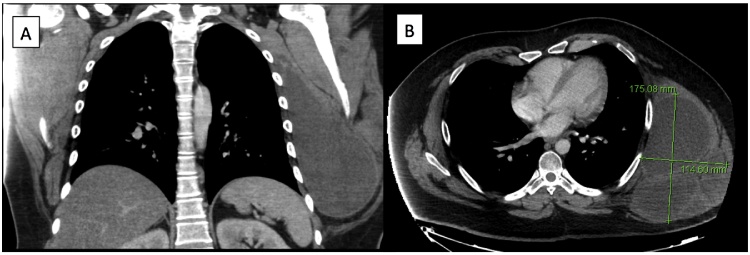

A 29 year old male presented to our thoracic surgery clinic with a left chest wall mass which he reported to be growing over the past year. The patient decided to seek medical treatment when he developed a mild pain at the site of the mass one-week prior to his presentation. On exam, the patient had a large chest wall mass. A computed tomography (CT) scan of the chest showed a 17.5 cm × 11.5 cm large lobulated mass, and a positron emission tomograph (PET)-CT showed uptake at the mass with an standardized uptake value (SUV) of 6.7 with no evidence of metastatic disease. He underwent a biopsy that was positive for sarcoma. The case was presented at the multidisciplinary thoracic tumor board, and given the size of the mass, he was recommended to undergo induction radiation therapy followed by surgery and subsequent chemotherapy. The mass continued to grow in size despite undergoing 50 Gy of radiation therapy. Patient then underwent an en-bloc resection of the mass with a 2 cm margin (R0 resection) arising from the serratus muscle with partial resection of lattisimus muscle. The ribs were not involved, and thus no chest wall resection was performed. A latissimus and serratus muscle primary reconstruction was performed by plastic surgery to cover the large defect. Final pathology showed a 27 cm × 16 cm × 16 cm high-grade (grade 3) fibrosarcoma with prominent myxoid component. To our knowledge, this is the largest STS of the chest wall reported in the literature. Six weeks later, the patient received 6 cycles of ifosfamide and adriamycin. The patient had disease free survival for 12 months, after which he developed metastatic disease in the lung and the pleura without evidence of local recurrence (Fig. 1, Fig. 2).

Fig. 1.

Preoperative CT scan demonstrates large chest wall mass on (a) coronal and (b) axial views.